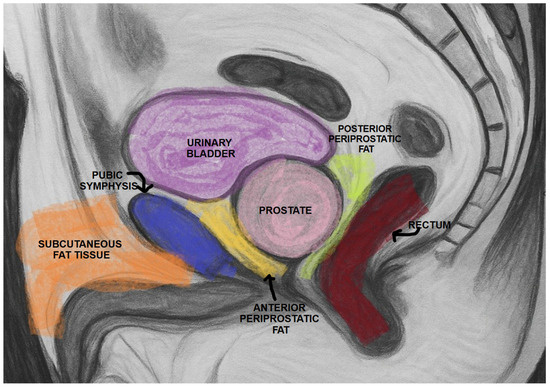

PPATT was measured as the shortest vertical distance from the pubic symphysis to the anterior surface of the prostate on midsagittal images; SATT was measured on the same slice as PPATT, defined as the shortest vertical distance from the pubic symphysis to the overlying skin, while PPPATT was measured as the shortest distance from the posterior surface of the prostate and anterior wall of the rectum. The images below represent the visual explanation of these measurements (Figure 2 and Figure 3).

Figure 2. Measurement of PPAT (red line), posterior PPAT (yellow line), and SATT (green line) on a midsagittal view, T2 sequence, on a prostate MRI categorized as PI-RADS 2, showing a prostate containing a well-defined prostatoc cyst.